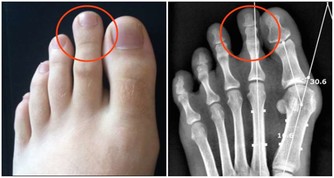

超聲科醫師檢查發現其右側陰囊空虛,右側腹股溝內可見大小約2*2*1cm的類睾丸迴聲,診斷考慮:隱睾症。

正常睾丸大小約4*3*2cm,位於陰囊內,

目前超聲檢查是最簡便,快捷無創的檢查方法,它不僅可檢查隱睾所在的位置,還可測量隱睾大小。